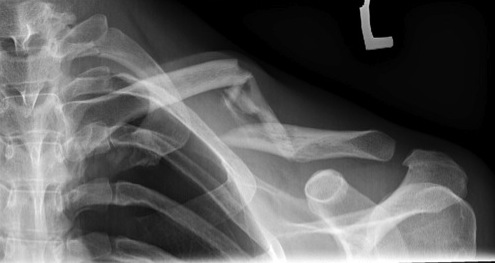

Compound clavicle fracture

Shorted / displaced midshaft clavicle fractures

Z shaped midshaft clavicle fracture